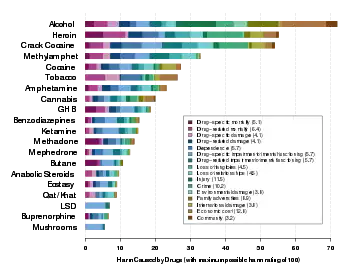

.jpg.webp)